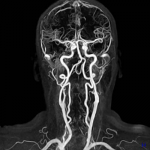

3D ASL

Estudios cuantitativos de la perfusión cerebral sin medio de contraste. Aprovecha el agua presente en la sangre arterial como medio endógeno de contraste para visualizar la perfusión tisular y realizar un análisis cuantitativo del flujo sanguíneo cerebral